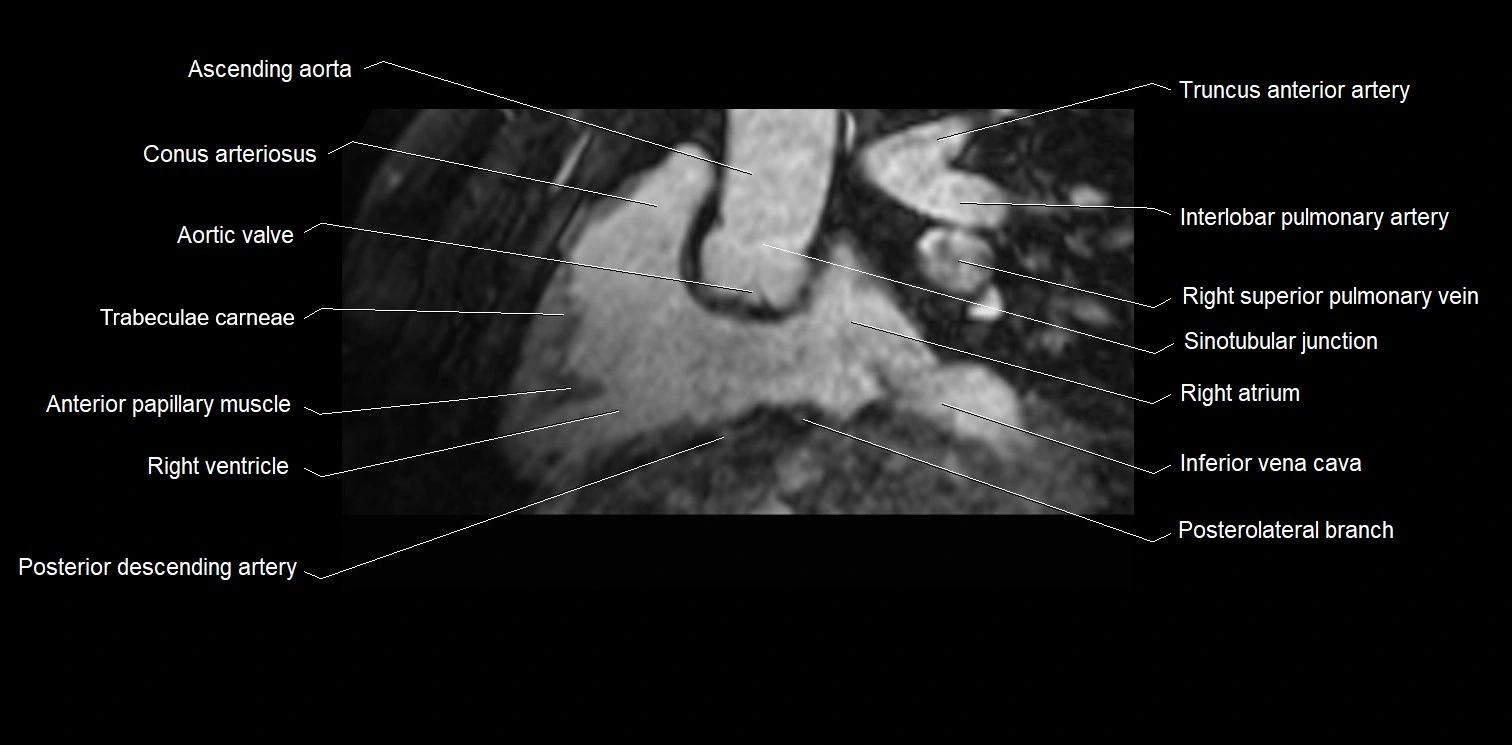

- Ascending aorta

- Conus arteriosus

- Aortic valve

- Trabeculae carneae

- Anterior papillary muscle

- Right ventricle

- Right posterior descending coronary artery (Right PDA)

- Inferior vena cava

- Right superior pulmonary vein